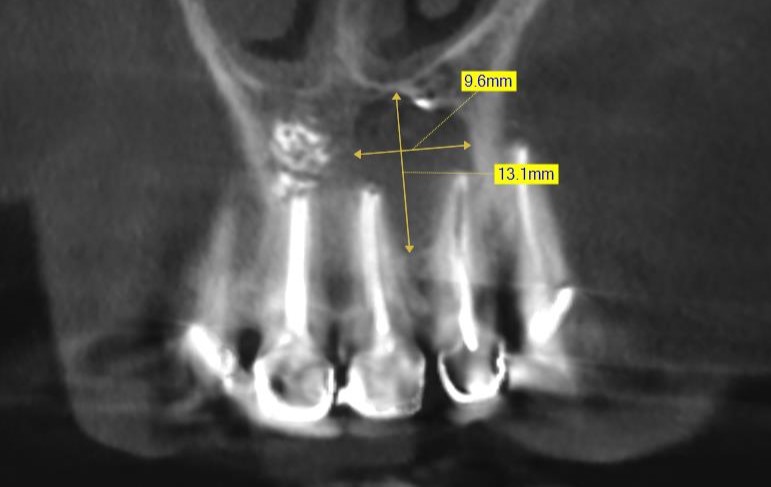

ЗД исследование перед операцией. Виден обьемный дефект в области зубов 21, 22 с вовлечением резцового канала. Размеры

Размеры кисты около1,3 мм в диаметре